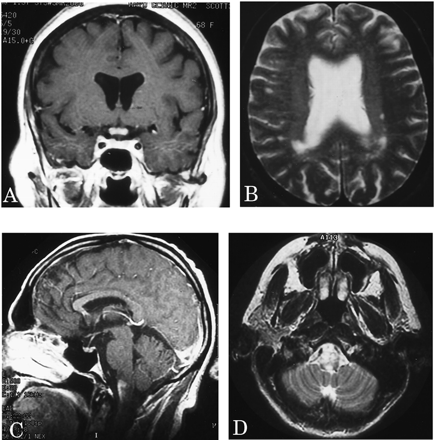

MRI:大脑。

特征典型的或明显的动了图4。脑部核磁共振进行了28 patients-27复发和1单相。中间间隔从第一个索引事件最初的大脑核磁共振是7.5个月(范围0.5 - 194)。视神经增强被认为在5 6例(83%)在2周内学习的一集。大脑实质是正常的在22个28初始扫描(79%);只有3 28(11%)满意的标准徽章等。10女士三个病人增加了T2信号在相邻的髓质纵向广泛的上颈椎脊髓损伤(见图4中,C和D)。

图4。选择先生大脑的图像。(A)扩散增强视神经交叉的gadolinium-enhanced t1日冕图像。(B)几室周的病变中看到一个病人在t2加权图像轴。(C和D)损伤扩展的吻侧颈绳在髓质gadolinium-enhanced t1矢状轴向和t2加权图像。

十六个复发患者多个大脑核磁共振;最初的扫描是正常14。后续核磁共振成像显示,7仍然正常(第一个和最后一个MRI的平均时间间隔,11个月;范围1 - 39)6开发了非特异性异常,不符合标准的徽章等。10女士(平均间隔23个月,范围3 - 85),和1个病人“转换”来满足女士标准103个月后。